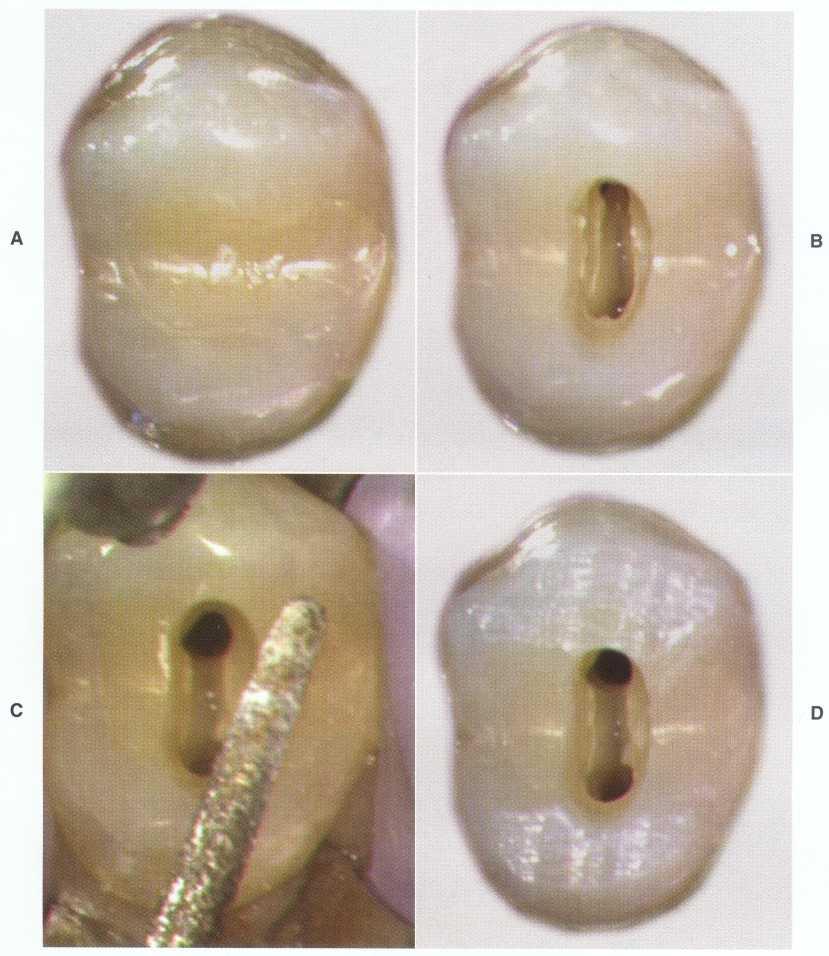

Treatment of maxillary molars is never routine (Figure 2-22). In a recent study of maxillary first and second molars an MB2 canal was found in 96% of the mesiobuccal roots of maxillary first molars and 94% of the maxillary second molars. Approximately 54% were located in the traditional access opening, 31% were found with the use of a bur, and 10% were found with the aid of a microscope. The MBZ canal orifice was found on average 1.82 mm lingual to the main MB canal orifice.9 In another study of the maxillary first molar using microscopy, the MB Z canal was located in

93% of first molars and 60% of second molars4 (Figures 2-23 and 2-24). The difficulty in access, high percentage of fourth and even fifth canals, and root curvatures put even the "routine" maxillary molar in a high-risk category.3 Complicating factors such as limited opening, crowns, changes in tooth angulation, tooth position, and calcification make predictable treatment of these teeth challenging for even the most experienced clinician trained in microscopy, ultrasonics, and rotary instrumentation.

FIGURE 2-24 The location of the MB 2 canal is mesial to the line connecting the MB and palatal orifice. In the maxillary first molar the MB2 canal is generally located within the range shown. In the maxillary second molar the location of the MB 2 s highly variable and can be located from the MB orifice to the palatal orifice (see Figs. 2-46 and 2-47).

Guidelines for canal location in the maxillary first molar (Figure 2-25) differ from that in the maxillary second molar. In the maxillary first molar the MB canal is located under the mesial buccal cusp (see Figure 2-25, D). The MBZ canal is located mesial to a line from the

MB canal toward the palatal canal (see Figures 2-25, E, and 2-26). The DB canal is located distal to the MB canal in the buccal groove area, slightly lingual to the MB canal (see Figure 2-25, G). The palatal canal is generally the largest canal and is located under the mesiolingual (ML) cusp (see Figure 2-25, F). These general locations remain the same as the pulp calcifies with age (Figure 2-27). Although these general principles apply to the maxillary second molar, the chamber may be narrower, resembling a straight line (see Fig. 2-55).